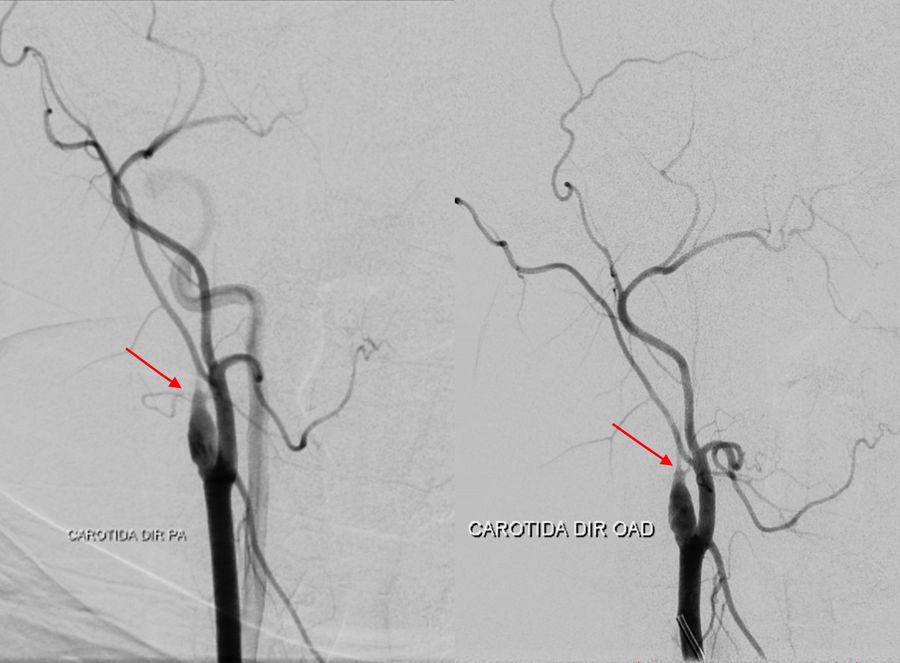

Catheter angiography was performed with the following findings:

• Occlusion at the proximal third of the cervical segment of the right internal carotid artery

• Stenosis of the supraclinoid segment of the left internal carotid artery

• Proximal stenosis of the anterior and middle cerebral arteries with collateral «smoke puff» vessels, which are characteristic findings of moyamoya disease

• Collateral circulation from the internal maxillary artery to the ipsilateral carotid territory

• Collateral irrigation of the carotid territory from the posterior circulation through a patent posterior communicating artery

A DSA (digital subtraction angiography) was performed pre-operatively to assess the occlusions of the internal and external

carotid arteries, as well as stenosis of the arteries and the feeding and draining blood vessels of the arteriovenous malformation, as

shown in the images below.